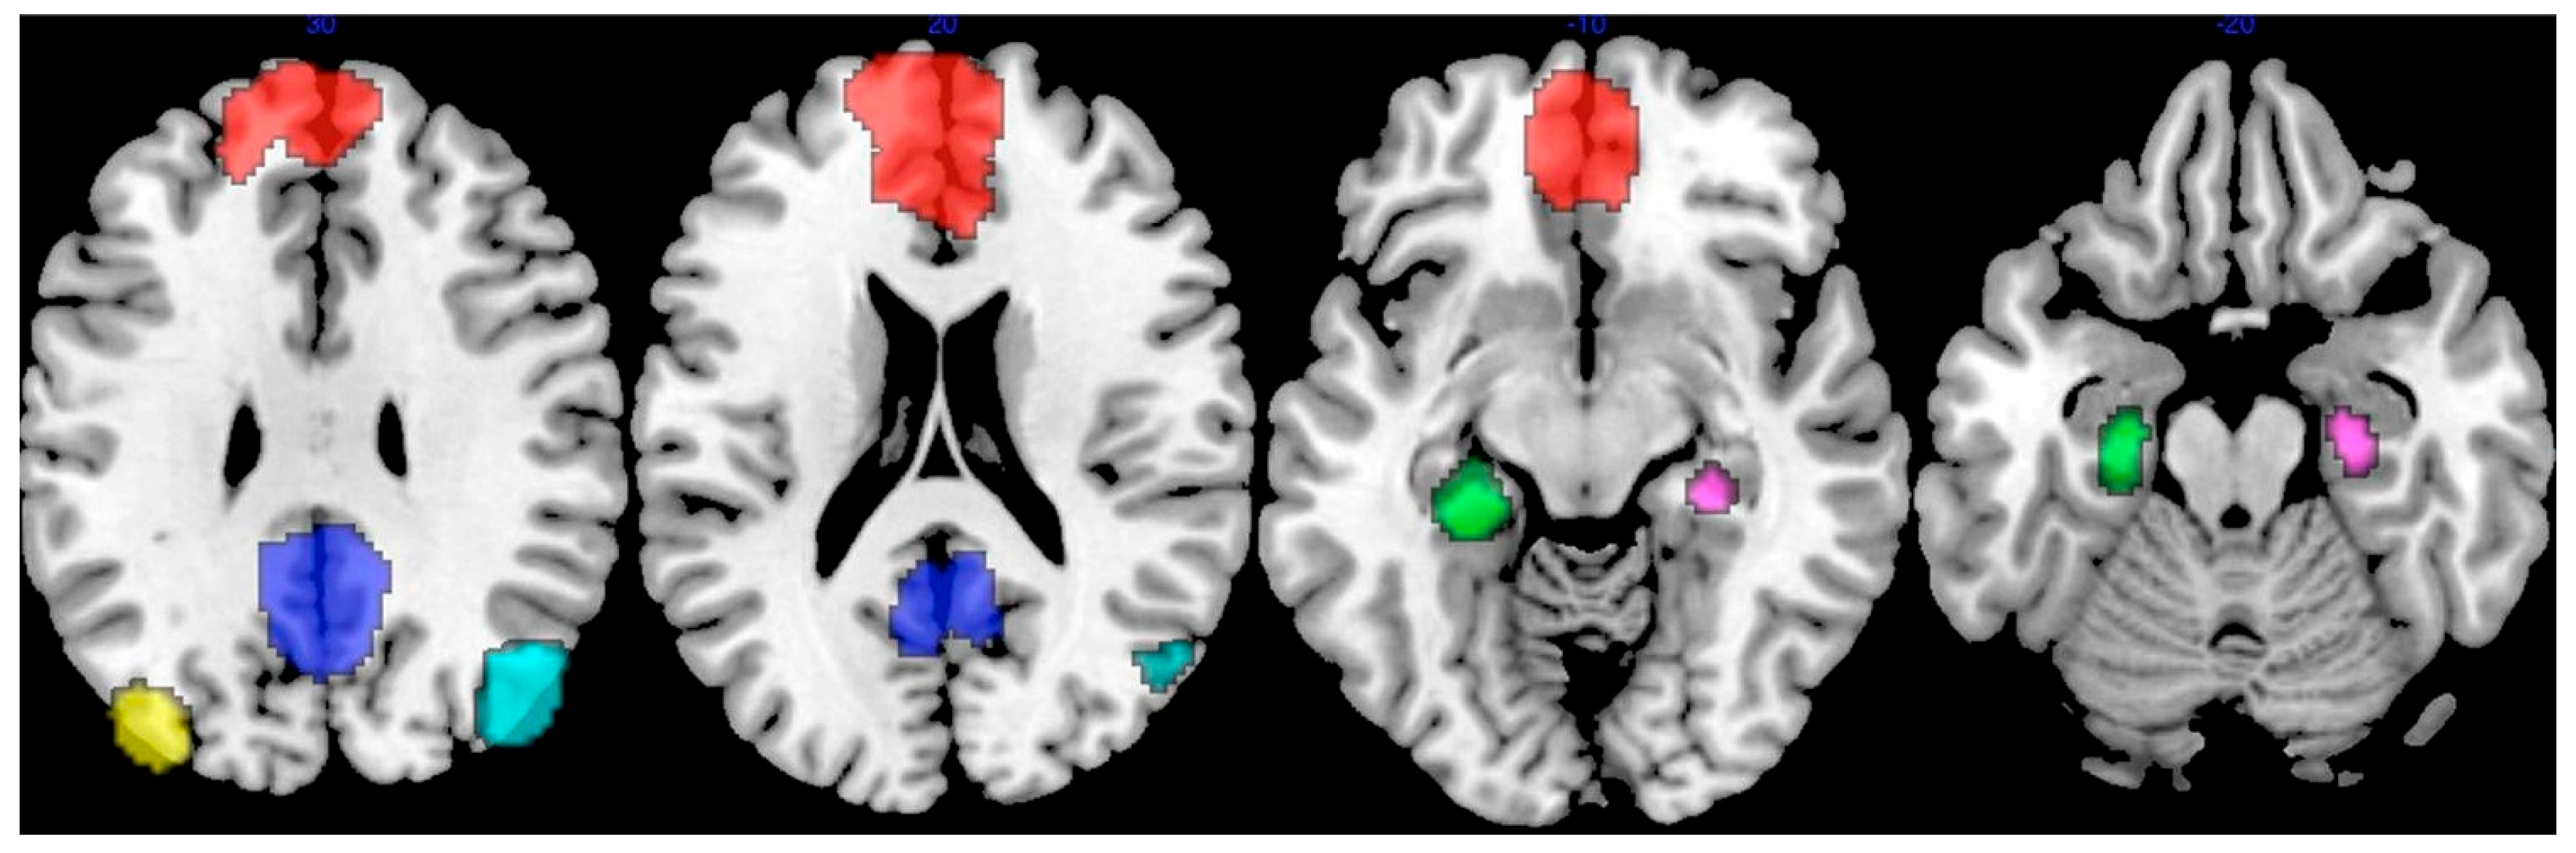

- Buckner, R.L.; Andrews-Hanna, J.R.; Schacter, D.L. The brain’s default network: Anatomy, function, and relevance to disease. Ann. N. Y. Acad. Sci. 2008, 1124, 1–38. [Google Scholar] [CrossRef] [PubMed]

- Seeley, W.W.; Menon, V.; Schatzberg, A.F.; Keller, J.; Glover, G.H.; Kenna, H.; Reiss, A.L.; Greicius, M.D. Dissociable intrinsic connectivity networks for salience processing and executive control. J. Neurosci. 2007, 27, 2349–2356. [Google Scholar] [CrossRef]

- Cole, M.W.; Reynolds, J.R.; Power, J.D.; Repovs, G.; Anticevic, A.; Braver, T.S. Multi-task connectivity reveals flexible hubs for adaptive task control. Nat. Neurosci. 2013, 16, 1348–1355. [Google Scholar] [CrossRef]

- Beckmann, C.F.; DeLuca, M.; Devlin, J.T.; Smith, S.M. Investigations into resting-state connectivity using independent component analysis. Philos. Trans. R. Soc. B Biol. Sci. 2005, 360, 1001–1013. [Google Scholar] [CrossRef] [PubMed]

- Thomas Yeo, B.T.; Krienen, F.M.; Sepulcre, J.; Sabuncu, M.R.; Lashkari, D.; Hollinshead, M.; Roffman, J.L.; Smoller, J.W.; Zöllei, L.; Polimeni, J.R.; et al. The organization of the human cerebral cortex estimated by intrinsic functional connectivity. J. Neurophysiol. 2011, 106, 1125–1165. [Google Scholar] [CrossRef]